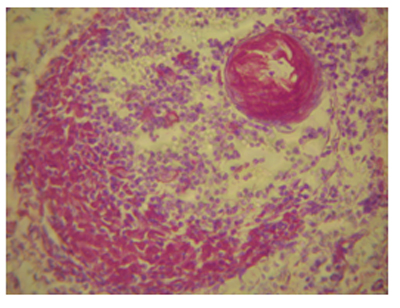

Արտամազանոթային պրոդուկտիվ գլոմերուլոնեֆրիտը, որն արտահայտվել է կիսալուսինների տեսքով նեֆրոթելի պրոլիֆերացիայով, 2 դեպքում զուգակցվել է երիկամային կծիկային հանգույցների ամիլոիդոզով (նկ. 7):

Նկ. 7. Արտամազանոթային պրոդուկտիվ գլոմերուլոնեֆրիտ` ուղեկցված կծիկային հանգույցների ամիլոիդոզով, հեմատոքսիլին-էոզին, x400